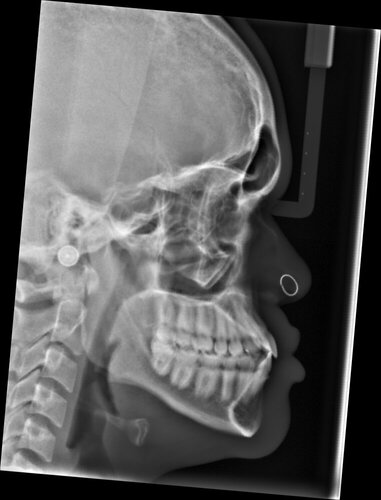

The upper maxilla mainly consists of the infra-orbital rims and the zygomatic bones (obviously there are more parts that make up the upper maxilla but these are the main things). If your upper maxilla is recessed, your infra-orbital rims along with your zygomatic bones are going to be recessed too. Therefore, if the upper maxilla is recessed in relation with the rest of your face, you're going to have hollow under eyes due to lack of bone support beneath the lower eyelids. As a result of a recessed maxilla, your zygomatic bones are also going to be recessed.

When people use the term "cheekbones", they refer to the zygomatic bones:

High set cheekbones are basically high set zygomatic bones. And low set cheekbones are basically low set zygomatic bones.